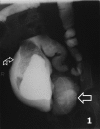

Congenital pouch colon is an anomaly always associated with anorectal malformation, where the colon is replaced by or terminates into a large aperistaltic intestinal pouch. Vertebral anomalies leading to neurogenic bladder are rare associated malformations. The pouch is aperistaltic and thus a poor rectal substitute but this very property makes it ideal for bladder augmentation. We report the first case where the pouch has been used to augment a high-pressure neurogenic bladder.